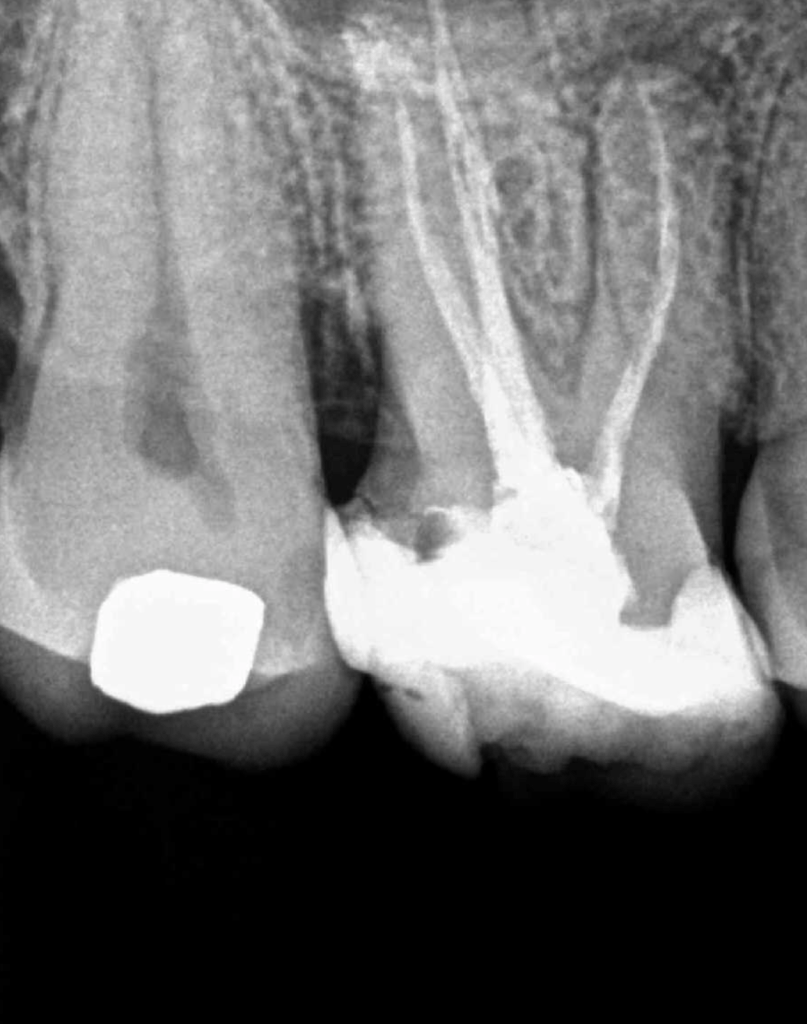

Retratamiento Primer Molar Superior